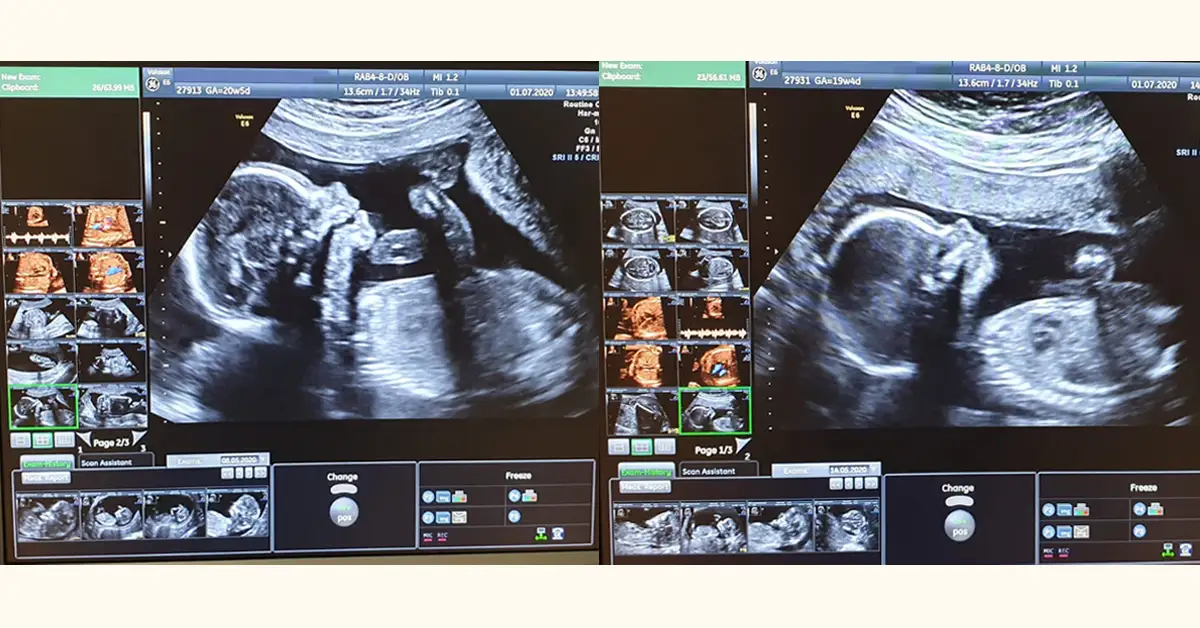

- USG genetyczne jest bezbolesne i trwa 20-30 minut, ocenia anatomię płodu oraz kluczowe markery, np. przezierność karkową (NT) i kość nosową (NB).

USG genetyczne to pierwsza i niezwykle ważna część testu złożonego. Dla Ciebie to po prostu bezbolesne badanie ultrasonograficzne, podczas którego możesz zobaczyć swoje dziecko na ekranie. Dla nas, lekarzy, to moment, w którym szczegółowo oceniamy anatomię płodu i szukamy kluczowych markerów genetycznych. To badanie jest niezwykle istotne w wczesnej diagnostyce, ponieważ pozwala nam dostrzec subtelne zmiany, które mogą wskazywać na podwyższone ryzyko wad genetycznych lub strukturalnych. Właśnie dlatego jest to jeden z najważniejszych elementów oceny zdrowia dziecka w I trymestrze.

Większość badań USG genetycznych w 12. tygodniu ciąży wykonujemy przez powłoki brzuszne. Jest to metoda nieinwazyjna i komfortowa dla większości pacjentek. Jednak w niektórych przypadkach, na przykład gdy obraz jest niewystarczająco wyraźny z powodu ułożenia płodu, budowy ciała matki, czy też w celu uzyskania bardziej precyzyjnych pomiarów, lekarz może zdecydować się na użycie sondy dopochwowej. Chcę Cię zapewnić, że obie metody są całkowicie bezpieczne dla Ciebie i Twojego dziecka i mają na celu jedynie uzyskanie jak najdokładniejszych informacji o jego rozwoju.

USG genetyczne jest badaniem całkowicie bezbolesnym. Trwa zazwyczaj od 20 do 30 minut, choć w niektórych sytuacjach, gdy dziecko jest mniej współpracujące (np. trudno je ułożyć do pomiarów), może potrwać nieco dłużej. Zapewniam Cię, że zarówno USG, jak i pobranie krwi na test PAPP-A, to procedury nieinwazyjne, które nie niosą ze sobą żadnego ryzyka dla rozwijającego się dziecka. Możesz być spokojna Twoje maleństwo jest bezpieczne, a my dbamy o to, by całe badanie przebiegło w atmosferze komfortu i zaufania.